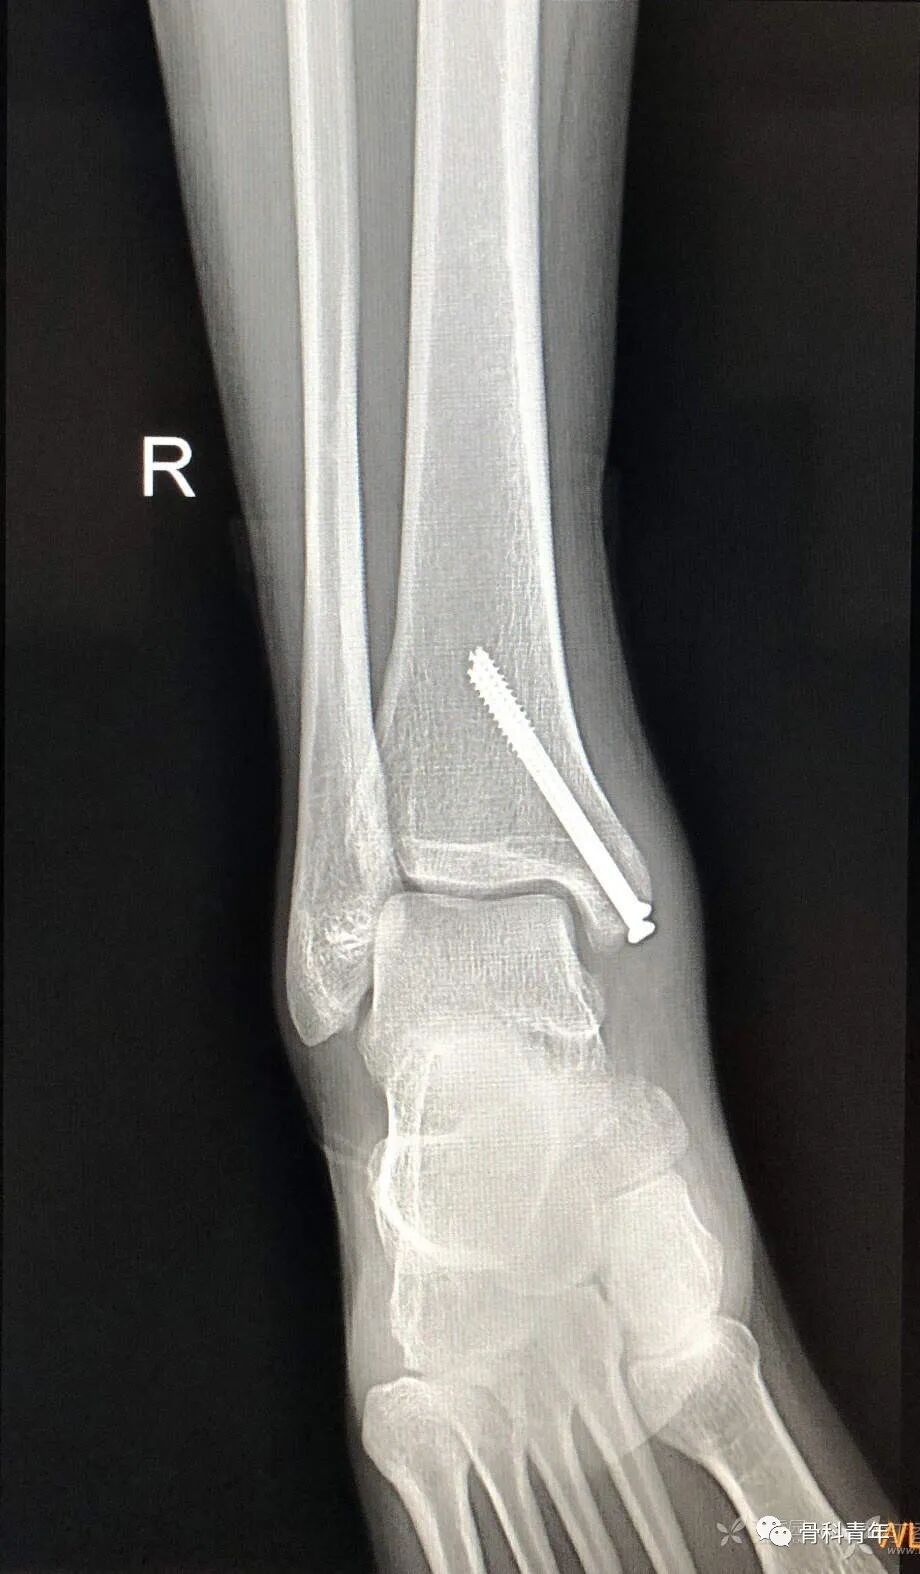

13.内踝骨折